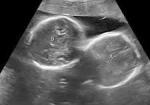

अल्ट्रासाउंड जांच में महिला के गर्भ में दो बच्चों की पुष्टि हुई थी